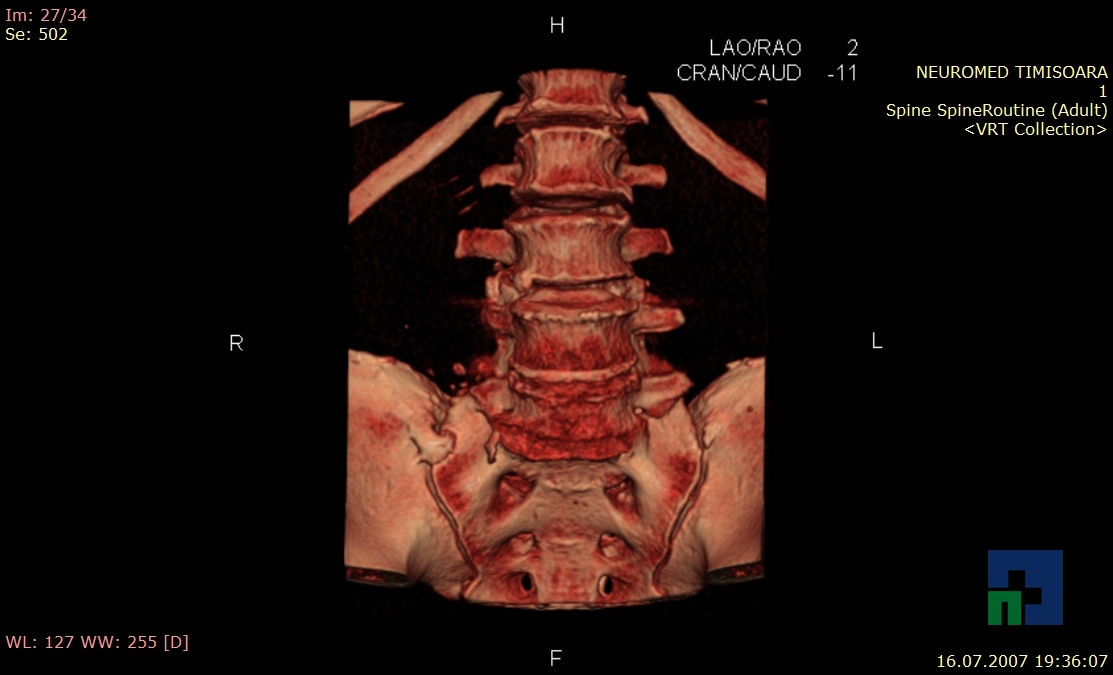

- Diagnosticul fracturilor:

-

- Unice

- Multiple

- Cu înfundare